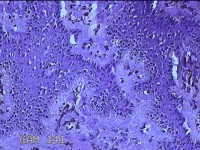

左侧臀部结节

性别

女

年龄

24岁

临床诊断

皮下结节

一般病史

发现左侧臀部结节1年余。

标本名称

大体所见

灰白暗红色带皮肤样结节0.7x0.3x0.2cm一个,表面糜烂,切开结节呈实性,切面灰白暗红色,质软。